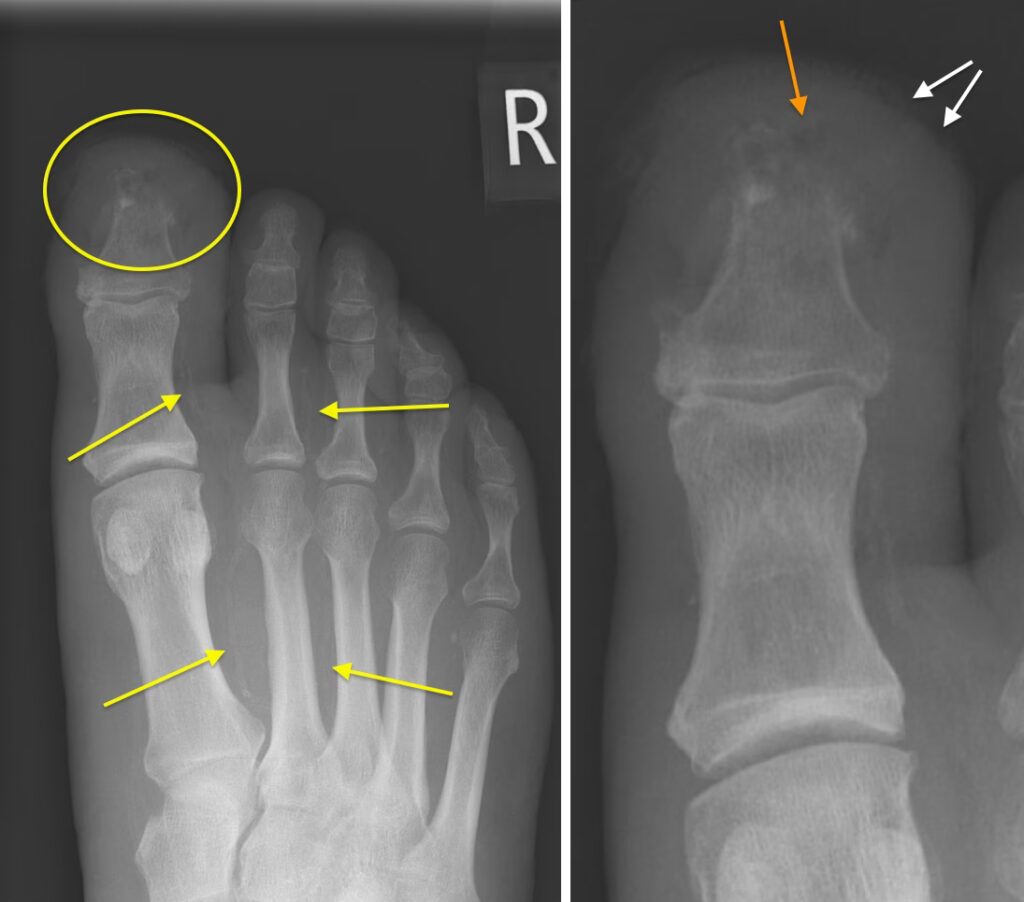

Diabetisk Fod

Den diabetiske fod er en alvorlig komplikation, der skyldes en kombination af neuropati (nedsat følesans) og perifer arteriesygdom. Et almindeligt røntgenbillede af foden er ofte den første undersøgelse og kan afsløre:

- Arteriel forkalkning: Forkalkninger i blodkarrene, et tegn på aterosklerose (åreforkalkning).

- Bløddelshævelse og sår: Kan indikere inflammation eller infektion.

- Charcot-fod: En alvorlig tilstand med progressiv ødelæggelse af knogler og led, som kan føre til svære deformiteter.

- Osteomyelitis: En infektion i knoglen, som er en hyppig og alvorlig komplikation til fodsår.

Selvom røntgen er vigtigt, anses MR-scanning ofte for at være guldstandarden for en tidlig diagnose af tilstande som Charcot-fod og osteomyelitis, da det giver en langt mere detaljeret fremstilling af både knogler og bløddele.

Hvilke tegn på diabetes kan ses på et røntgenbillede af foden?

Typiske fund inkluderer vaskulære forkalkninger, bløddelshævelse, tegn på knogleinfektion (osteomyelitis) og led-destruktion som ved en Charcot-fod. Disse fund er afgørende for at forhindre alvorlige konsekvenser som amputation.